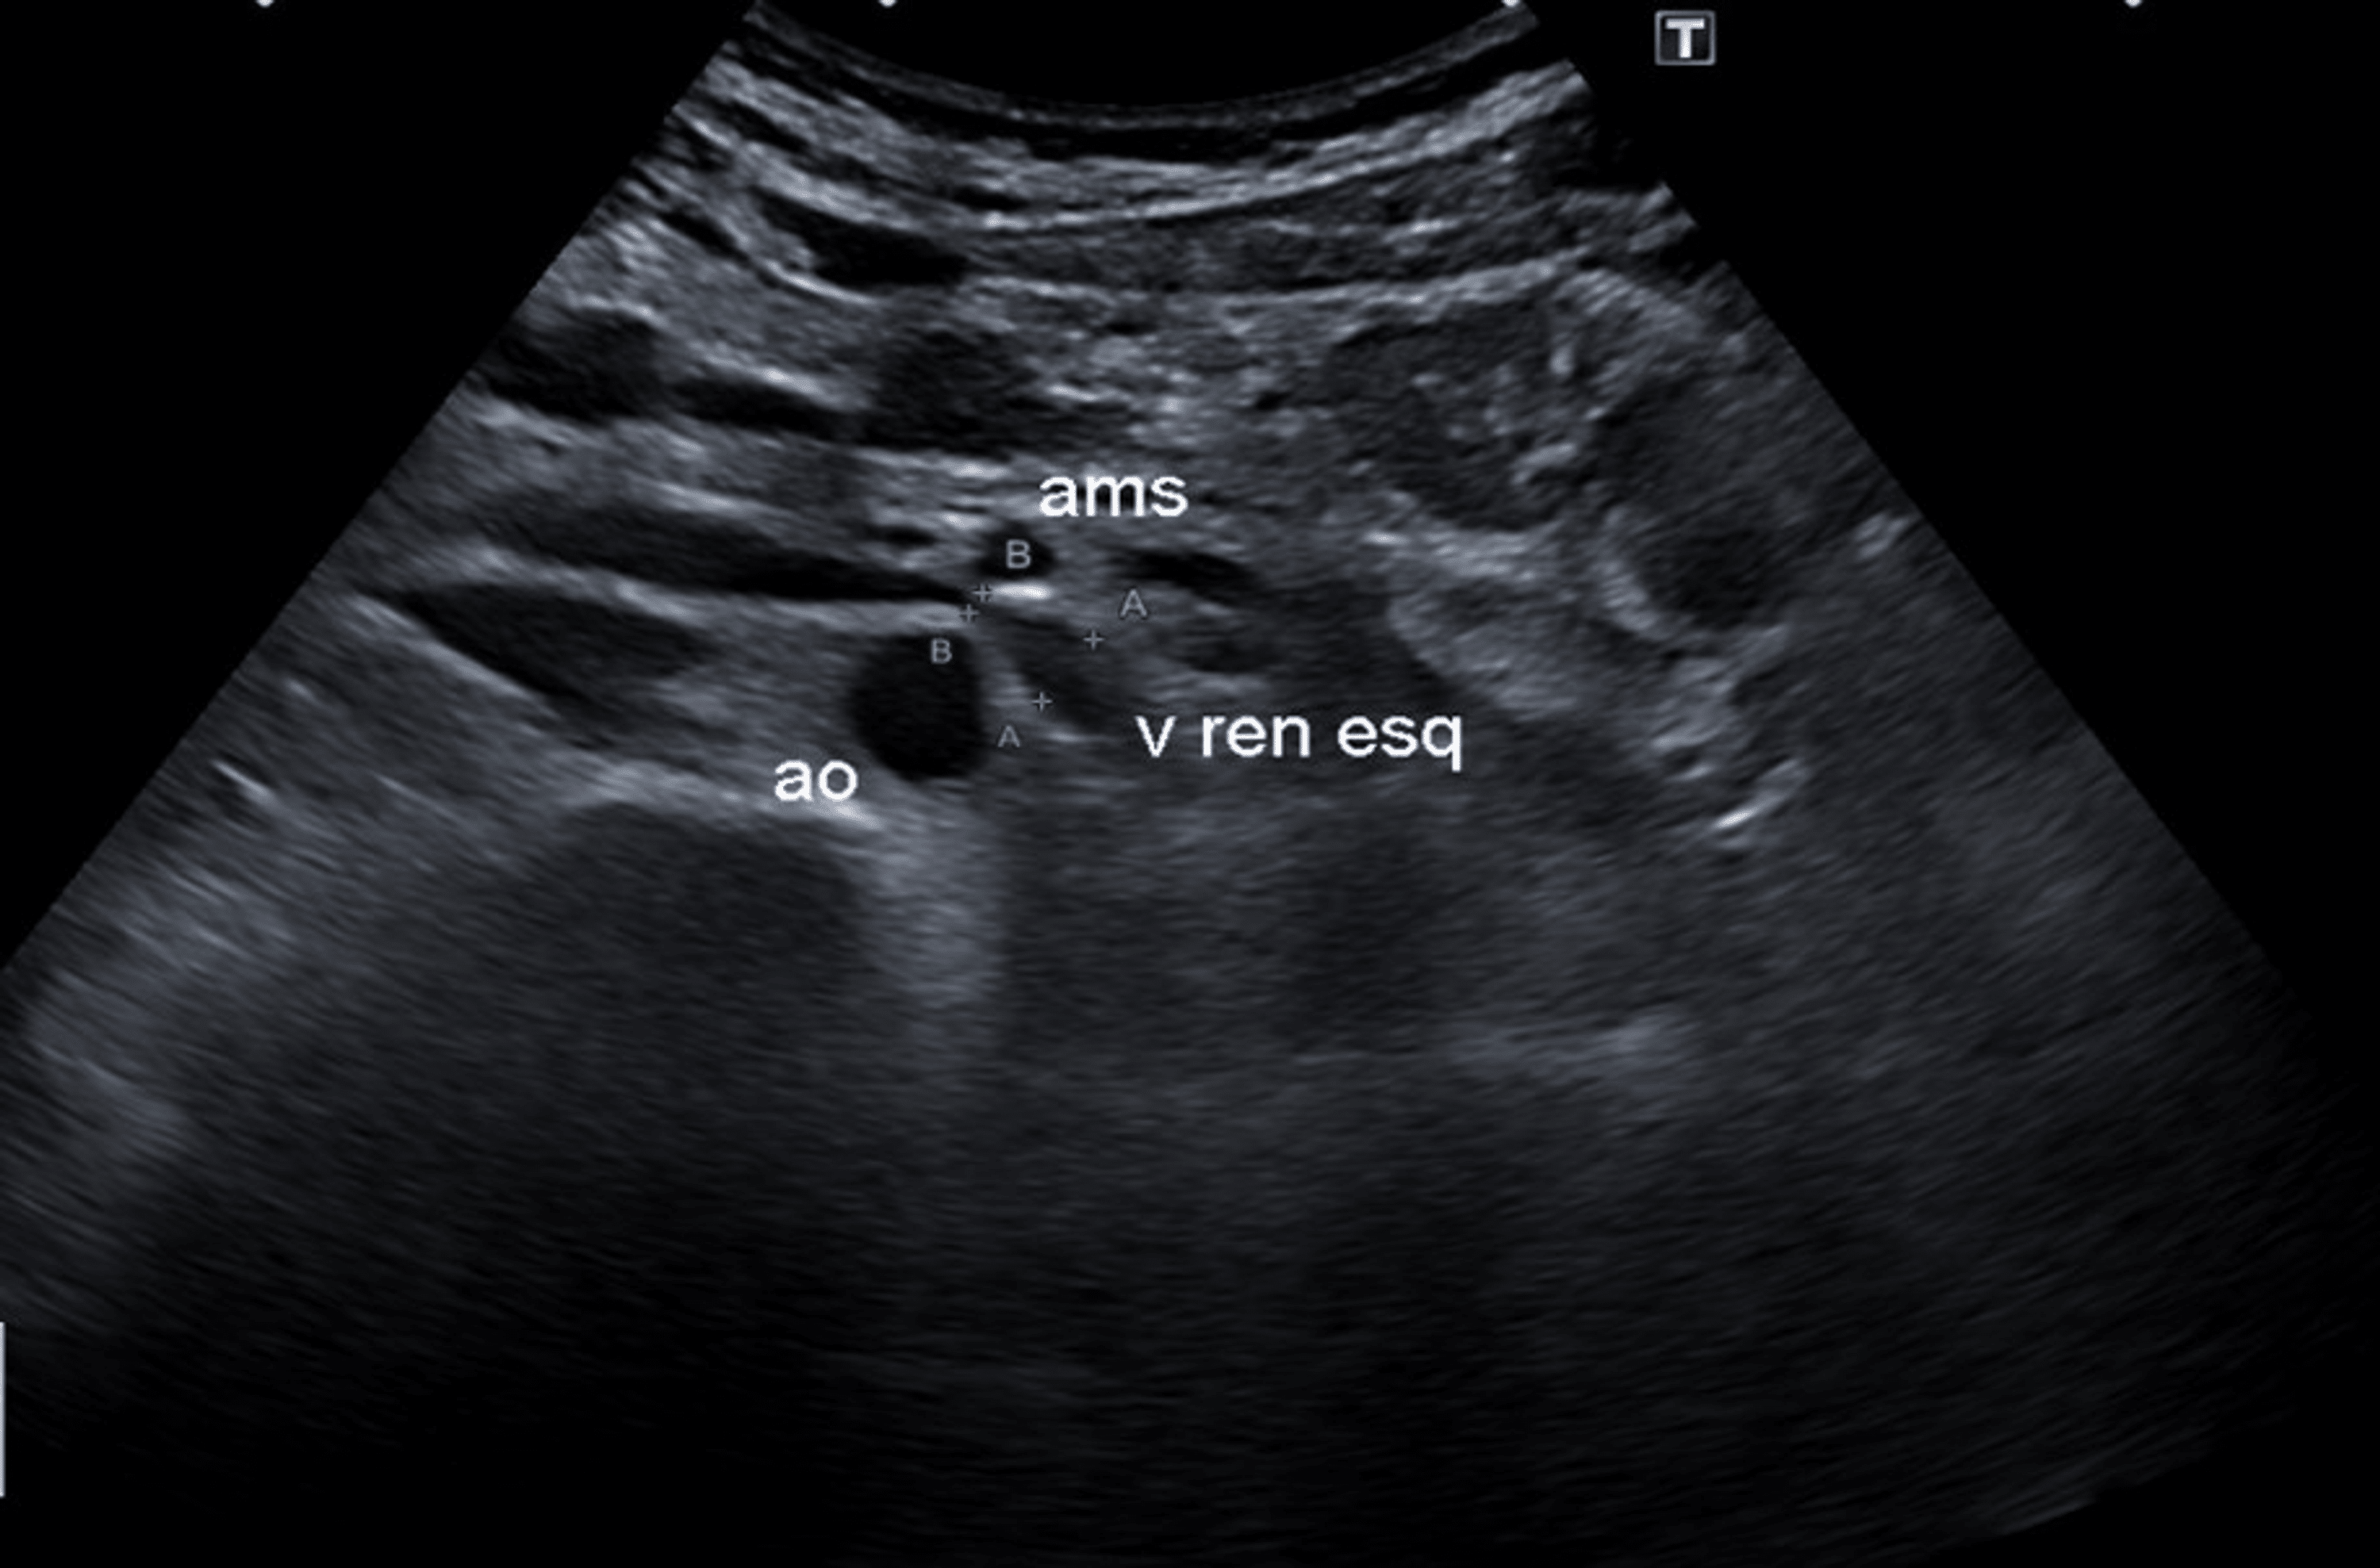

From sonographictendencies.com

Nutcracker Phenomenon/Syndrome Sonographic Tendencies Nutcracker Syndrome Back Pain Patients can be referred to a vascular surgeon due to symptoms and/or radiologic findings. Nutcracker syndrome (ncs) is a rare condition characterized by a group of clinical manifestations, like hematuria and pain, and is. It is a rare clinical entity, although probably underdiagnosed. Left renal vein (lrv) compression resulting in signs and symptoms is commonly known as nutcracker syndrome. This. Nutcracker Syndrome Back Pain.